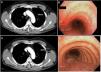

(A) Cross-sectional chest CT slice showing tracheal thickening, including measurement of the tracheal diameter. (B) Pre-treatment bronchoscopy showing lesions in the tracheal wall. (C) Cross-sectional CT slice following treatment with inhaled corticosteroids. (D) Bronchoscopy with no lesions after treatment, including measurement of the tracheal diameter.

He was referred to our clinic with a 1-month history of non-productive cough and fever. During the course of these symptoms, he received 2 antibiotic regimens, first with levofloxacin and then with amoxicillin-clavulanate. The chest X-ray showed no significant changes and pulmonary function tests were significant only for slightly altered diffusion results (FEV1 3,100 [91%]; FVC 3,550 [81%]; FEV1/FVC 87%; DLCO 71%; KCO 101%). Given the suspicion of infectious disease in an immunosuppressed patient, azithromycin was added to the treatment plan, and a computed axial tomography (CT) scan was performed, which revealed discreet tracheal wall thickening, with no evidence of pulmonary consolidations or other type of involvement (Fig. 1). The bronchoscopy was significant for raised whitish lesions in the tracheal wall and at the entrance of the two main bronchi, predominantly in the posterior tracheal wall (Fig. 1). An opportunistic infection was suspected, so bronchoalveolar lavage (BAL) was performed and samples were sent to the microbiology lab: standard pathogen panel (bacteria, mycobacteria, fungi, viruses, etc.) was negative. The pathology study of the tracheal wall biopsy reported nonspecific inflammatory signs with areas of ulceration. BAL cellularity consisted mainly of macrophages (80%), lymphocytes (15%) and polymorphonuclear cells (5%).

A diagnosis of tracheobronchitis due to Crohn’s disease was given. Treatment started with inhaled corticosteroids (fluticasone 1,000 mg every 12 h). After 1 month of treatment, the patient's symptoms had disappeared, so dosing was reduced to 500 mg every 12 h. A chest CT scan was repeated, in which chest wall thickening was no longer visualized. Bronchoscopy after treatment confirmed the resolution of the earlier lesions.